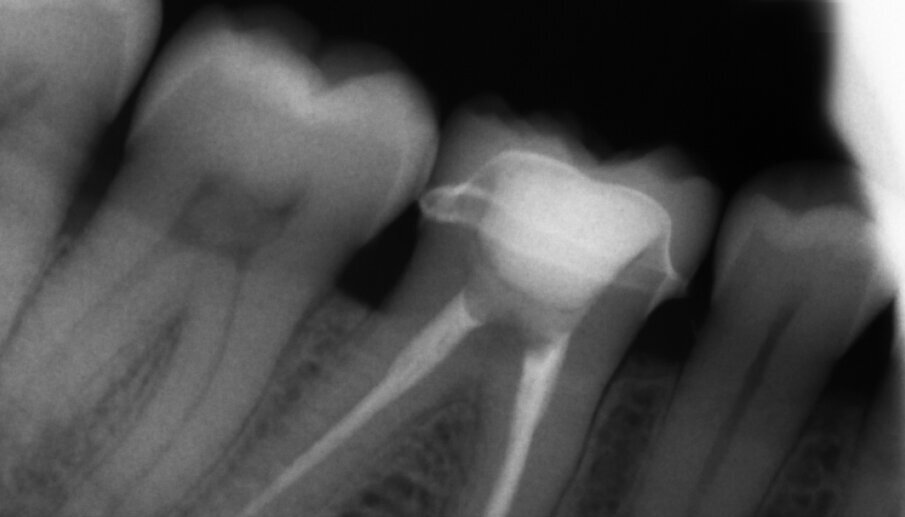

Figs. 13a & b: Radiographic control images before and after the treatment.

A 45-year-old male patient presented to the practice with a restoration on tooth #46. The tooth had been endodontically treated and temporised with a filling (Fig. 1). The temporary was removed, the tooth built up with Tetric N-Ceram Bulk Fill (Ivoclar Vivadent) and then prepared for the crown restoration (Fig. 2). An impression was taken with a one- step, two-phase impression technique using a putty and light-body silicone. After scanning the model, the crown was designed in the software suite (inLab, Dentsply Sirona) and milled from an IPS e.max CAD lithium disilicate block (Ivoclar Vivadent; Figs.3a & b). After the crystallisation fir- ing, the crown was stained and glazed (Fig. 4). The next step was to etch and silanate the ceramic crown with the new glass-ceramic primer Monobond Etch & Prime (Ivoclar Vivadent). This primer combines a ceramic etching and silanating component in a single material and therefore eliminates the need for the ceramic to undergo hydrofluoric acid etching (Fig. 5). After the etching and silanating step, the crown was rinsed with water and dried. The isolated enamel was then etched (Fig. 6). The adhesive (Tetric N-Bond Universal) was applied and dispersed with a strong stream of air. The dual-curing version of the Variolink Esthetic luting composite was used for seating owing to the thickness of the crown and the low translucency of the ceramic material (Fig. 7). The luting composite was applied into the crown. The restoration was then seated (Fig. 8) and light-cured from each side for two seconds. Excess composite was easy to remove owing to the Ivocerin photoinitiator (Ivoclar Vivadent), which provides a fast and thorough cure with a minimum amount of energy (Fig. 9). For final polymerisation, the restoration was light-cured from each quarter for 20 seconds (Fig. 10). Figures 11 and 12a & b show the oral situation after placement of the crown. Although the cement line was located above the gingival margin, it was not visible owing to the favourable tone and opacity of the luting composite. Figures 13a & b show radiographic control images of the restoration: the radiopaque build-up material and cement can easily be distinguished from the tooth structure. This aspect is particularly important in situations where excess cement cannot be seen with the naked eye.